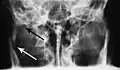

Towne's view of a bilateral condyle fracture. White arrow is a fracture on the neck of the condyle. Black arrow shows the condyle pulled to the medial. The same injury can be seen on the opposite side -

Traditionally, plain films of the mandible would be exposed but had lower sensitivity and specificity owing to overlap of structures. Views included AP (for parasymphsis), lateral oblique (body, ramus, angle, coronoid process) and Towne's (condyle) views. Condylar fractures can be especially difficult to identify, depending on the direction of condylar displacement or dislocation so multiple views of it are usually examined with two views at perpendicular angles.[11]